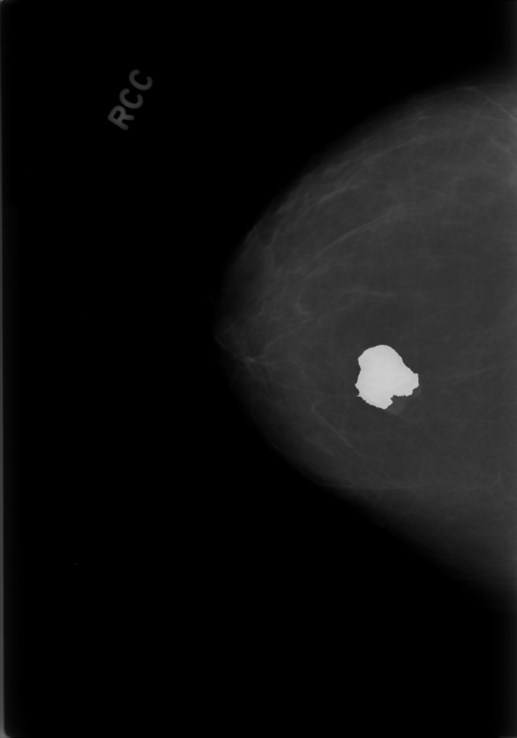

Breast cancer is the most widespread neoplasm among women and early detection of this disease is critical. Deep learning techniques have become of great interest to improve diagnostic performance. Nonetheless, discriminating between malignant and benign masses from whole mammograms remains challenging due to them being almost identical to an untrained eye and the region of interest (ROI) occupying a minuscule portion of the entire image. In this paper, we propose a framework, parameterized hypercomplex attention maps (PHAM), to overcome these problems. Specifically, we deploy an augmentation step based on computing attention maps. Then, the attention maps are used to condition the classification step by constructing a multi-dimensional input comprised of the original breast cancer image and the corresponding attention map. In this step, a parameterized hypercomplex neural network (PHNN) is employed to perform breast cancer classification. The framework offers two main advantages. First, attention maps provide critical information regarding the ROI and allow the neural model to concentrate on it. Second, the hypercomplex architecture has the ability to model local relations between input dimensions thanks to hypercomplex algebra rules, thus properly exploiting the information provided by the attention map. We demonstrate the efficacy of the proposed framework on both mammography images as well as histopathological ones, surpassing attention-based state-of-the-art networks and the real-valued counterpart of our method. The code of our work is available at https://github.com/elelo22/AttentionBCS.